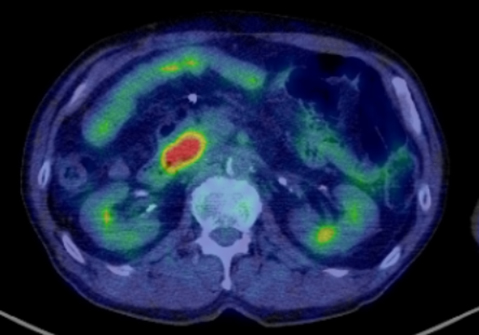

FDG-PET所見:膵頭部にSUV max 8.8の異常集積を認めた(Fig. 5).

FDG-PET showed increased FDG uptake in the pancreatic head (SUV max 8.8).